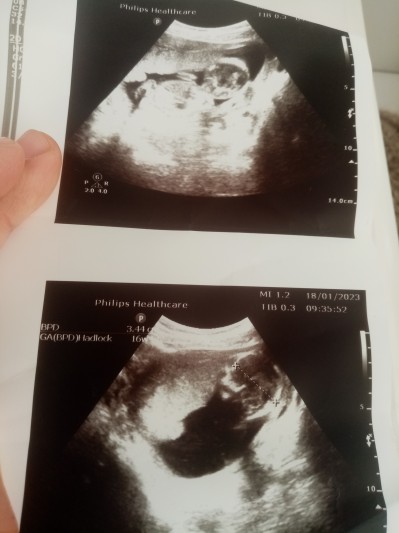

19 Ocak 2023 Hamilelikte Anne Sağlığı kategorisinde (10 puan) sordu

bebeğin plesentasi aşağıda, buyuzden bebek bacağını tam acamiyor denildi bu nedir ya i plesenta yukarı çıkar mı 16 haftalik

image